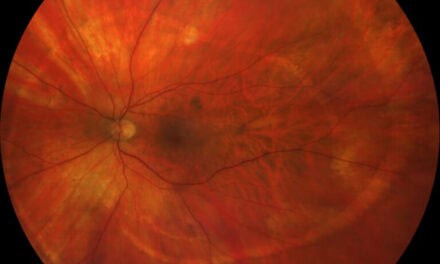

LatestPhoto Essay – A Spiral Illusion: An Atypical Presentation of Schlaegel Lines

This case describes an unusual spiral pattern of Schlaegel lines in a patient with inactive multifocal choroiditis. Although most often associated with...

Photo Essay – A Spiral Illusion: An Atypical Presentation of Schlaegel Lines

by Theresa Jay, OD, FAAO, Steve Njeru, OD, MS, FAAO and Melissa Chen, OD | Aug 19, 2025

This case describes an unusual spiral pattern of Schlaegel lines in a patient with inactive multifocal choroiditis. Although most often associated with...

Photo Essay – A Spiral Illusion: An Atypical Presentation of Schlaegel Lines

by Theresa Jay, OD, FAAO, Steve Njeru, OD, MS, FAAO and Melissa Chen, OD | Aug 19, 2025 | Photo Essay, Retina, Volume 3, Issue 3 | 0 |

This case describes an unusual spiral pattern of Schlaegel lines in a patient with inactive multifocal choroiditis. Although most often associated with...